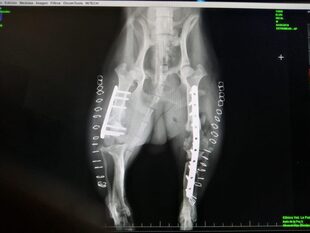

Röntgenbild Elvis nach der OP

Inzwischen ist Elvis erfolgreich operiert worden und bei seiner neuen Familie in Deutschland eingezogen. Es wird noch ein wenig dauern bis er wieder richtig flitzen kann und vielleicht wird er immer ein bisschen unrund laufen, aber ab jetzt liegt eine große glückliche Zukunft vor ihm...